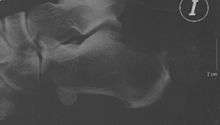

After evaluating the patient's symptoms, the foot and ankle surgeon will examine the foot. In addition, x-rays will be requested to help the surgeon evaluate the structure of the heel bone.